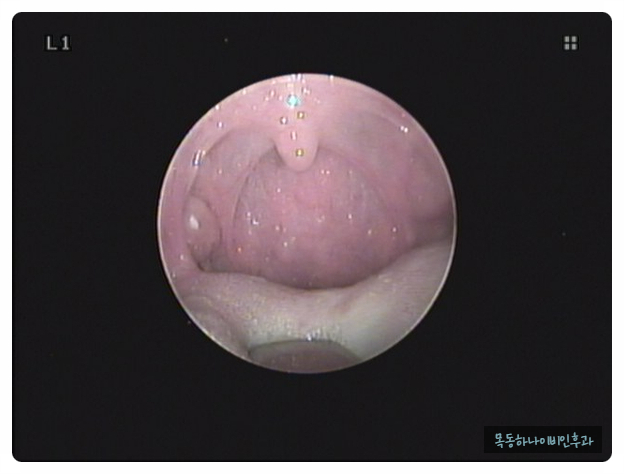

편도결석은 편도선 안에 있는 얇고 깊은 홈에 음식물 찌꺼기나 각종 분비물이 침착하여 돌처럼 단단해진 물질입니다. 크기는 눈곱처럼 작기도 하지만 손톱 크기 정도의 큰 결석이 나오기도 합니다. 색깔도 다양하고 흰색에서 노란색이나 치즈색을 보이기도 합니다. 건강한 성인에서도 약 10%에서 편도결석이 관찰됩니다. 물론 편도 결석이 있습니다만, 결석이 있다는 것을 알지 못하는 분도 많습니다.

편도 결석은 암이나 나쁜 질환으로 진행되는 병이 아닙니다. 증상이 없는 결석의 경우 특별한 치료 없이 관찰하셔도 좋습니다. 하지만 구취나 목에 물감이 있는 경우는 치료를 생각할 수 있습니다.